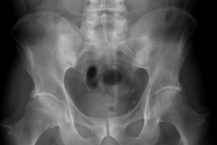

Tin tứcHướng dẫn chụp X-quang khung chậu thẳngTác giả: Trần Như Tú,Nguyễn Hữu Xuân,Trần Thị Thanh Thủy | Ngày xuất bản: 14/06/2022 Hướng dẫn chụp X-quang khung chậu thẳng áp dụng cho các khoa Chẩn đoán hình ảnh trong toàn hệ thống Vinmec